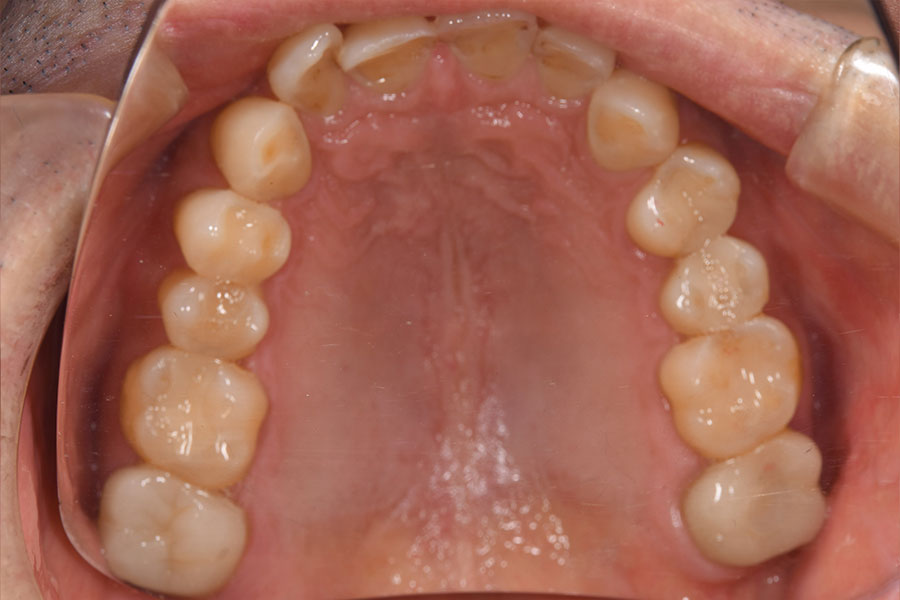

After -上顎-

| 施術内容 | 金属アレルギー予防を目的に、金属フリーの自費補綴へ変更。適合性・清掃性・審美性の向上が得られています。 |

|---|---|

| 治療期間 | 約4ヶ月 |

| 費用 | ハイブリットクラウン ハイブリットインレー 693,000円 |

| リスク・副作用 | 治療にともない、歯の破折や歯質の削合、場合によっては抜歯が必要となることがあります。また、金属や補綴物を除去する際に、完全に除去できない場合もあります。 |